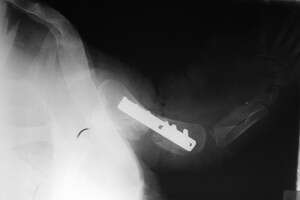

הם ביצעו ניתוח ראשון מסוגו בישראל, תוך שקיבעו את עצם הזרוע השבורה בעזרת פלטת מתכת וברגים. למען עידוד האיחוי, הכניסו שתל עצם שנלקח מהשריון.

צילום רנטגן לאחר הניתוח. צילום: ד''ר צחי אייזנברג, מרפאת כל חי דר צחי אייזנברג – מרפאת כל חי